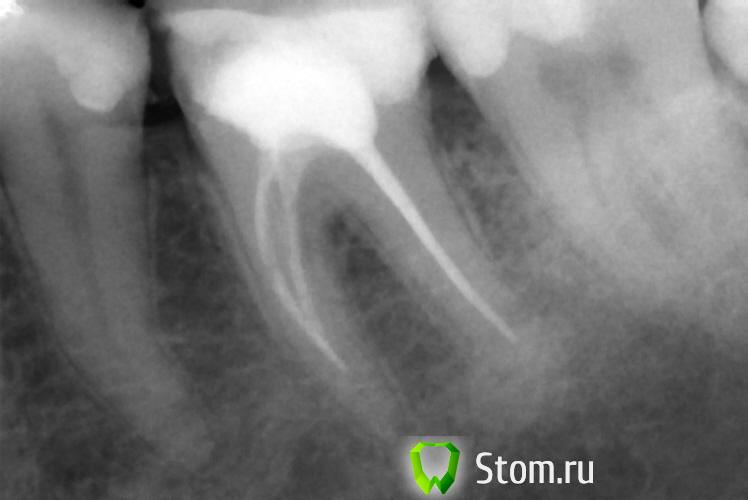

x3m Опубликовано 9 февраля, 2012 Поделиться Опубликовано 9 февраля, 2012 это снимки после лечения каналов?? Ссылка на комментарий

beshdr Опубликовано 9 февраля, 2012 Автор Поделиться Опубликовано 9 февраля, 2012 Да. Ссылка на комментарий

pawa Опубликовано 9 февраля, 2012 Поделиться Опубликовано 9 февраля, 2012 Однокорневые вкладки не проблема, пломбировка корневых каналов неудовлетворительная. Ссылка на комментарий

beshdr Опубликовано 13 февраля, 2012 Автор Поделиться Опубликовано 13 февраля, 2012 Всегда любая отрасль идет по пути наращивания прибылей - стоматология не исключение - и если теперь используют такие материалы, которые через 10 лет рассасываются в канале и требуют повторной перепломбировки - значит скоро будут использовать те, которые рассасываются через 5. Мои каналы я делала 10 лет назад, тогда мне их заделали какой-то пастой на основе цемента и фактически уже тогда зубы были подготовлены к протезированию, причем без всяких корневых вкладок! Сейчас, чтобы распломбировать по 1 каналу в каждом зубе - терапевту потребовался 1 час времени! Реально, там все окаменело. Думаю, эта паста никуда не должна рассосаться, на снимках, возможно, это не так хорошо видно, как если бы каналы были запломбированы гуттаперчей. В общем - всячески себя утешаю, надеюсьь и верю в то, что все будет хорошо и все сделано правильно. Сколько зубов - столько и мнений ))) Ссылка на комментарий